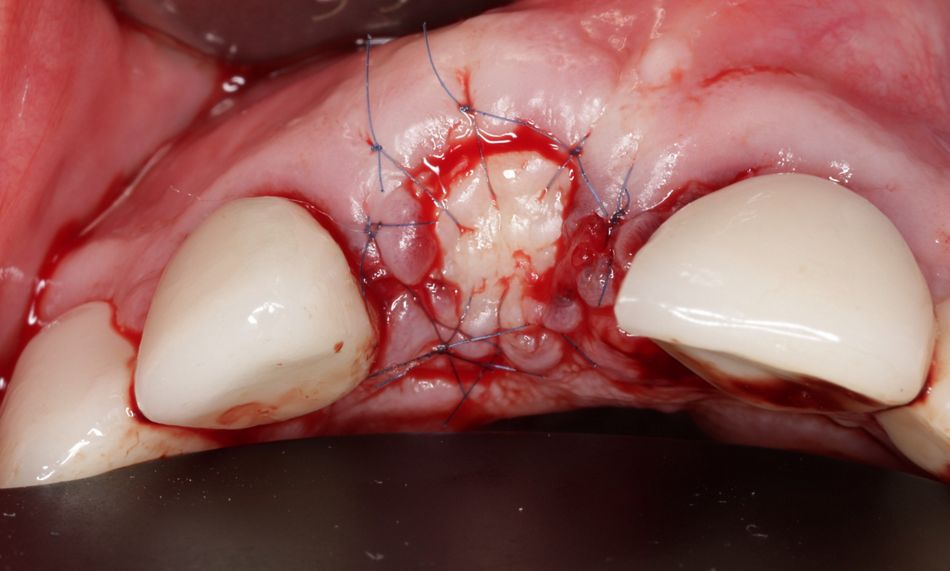

Für ein optimales Weichgewebemanagement und eine adäquate Rot-Weiß-Ästhetik sollte die keratinisierte periimplantäre Mukosa chirurgisch erhalten werden. Hierfür wurden aus dem hinteren Gaumenbereich zwei freie Schleimhauttransplantate (FST) entnommen (Abb. 10) und auf einer Glasplatte mit dem Skalpell entepithelisiert. Die Spenderregion ist mit einem Histoacryl-Kleber primär verschlossen worden. Die entsprechend vorbereiteten Transplantate wurden bukkal und oberhalb der Insertionsstelle hier als Punch mit Einzelknopfnähten (07 Seralene) vernäht und so das gingivale Gewebe maximal gestützt und erhalten werden (Abb. 11).